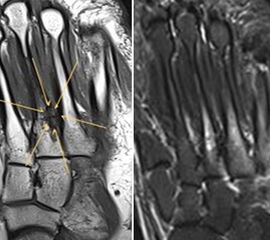

Abbildung 2.1.

Bildbeispiele symptomatische OCL

Zum Lesen der Bildbeschreibung und zur Vollansicht bitte das Bild anklicken. Bild: H. C. Rischke

Abbildung 2.2.

Bilder eines Patienten mit Z. n. mehrfachen Sprunggelenksdistorsionen in der Vergangenheit, besonders heftige Distorsion des linken Sprunggelenkes 5 Wochen vor der Untersuchung. Die SPECT/CT zeigt eine instabile osteochondrale Läsion mit deutlicher Aktivierung.

Abbildung 2.3.

Klärung bei Schmerzen im rechten OSG bei OCL an der medialen Talusschulter. Z. n. OSG-Distorsion vor 2 Jahren und Z. n. OSG-Fraktur / Syndesomosenruptur. Ausgedehnte OCL, hier jedoch kein erhöhter Knochenmetabolismus; lediglich Nachweis einer Stressreaktion im Bereich der Synchondrose eines Os trigonum als Schmerzursache.